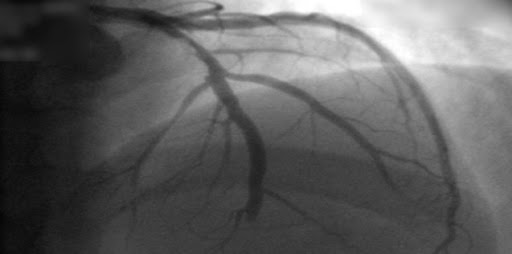

Estudios coronarios en la cardiopatía isquémica estable: ¿TC o cateterismo?

20 octubre 2022

Este estudio no encontró diferencia entre mujeres y varones en el beneficio del uso de la tomografía computarizada (TC) en lugar de la angiografía coronaria invasiva como prueba diagnóstica inicial para el manejo del dolor torácico estable en pacientes con una probabilidad previa a la prueba intermedia de enfermedad arterial coronaria. La TC inicial se asoció con menos complicaciones importantes relacionadas con el procedimiento en las mujeres y una frecuencia más baja del compuesto MACE expandido en los hombres.British Medical Journal, 19 de octubre de 2022.